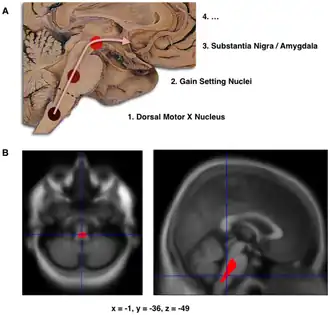

Braak staging

B. Localization of the area of significant brain volume reduction in initial PD compared with a group of participants without the disease in a neuroimaging study which concluded that brain stem damage may be the first identifiable stage of PD neuropathology.[1]